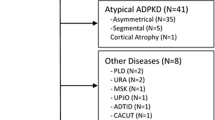

One hundred twenty-four patients (male 62, female 62) participated in the external validation study. Accurate KV, ellipsoid KV and Vincent KV were measured in all these patients. Patients’ characteristics were shown in Table 1. The mean age was 49.7 years old. The median eGFR was 46.9 ml/min/1.73 m2 (IQR 24.2–62.5). The most common CKD severity is stage 3 (n = 49, 39.5%). All patients received plain CT scan with varying thickness (median 0.63 ml, IQR 0.5–2) of kidney.

Median accurate KV was 627.7 ml (IQR 441.6–1035.0). There was no significant difference between rt. (median 624.6 ml, IQR 435.2–969.8) and lt. (median 651.1 ml, IQR 470.9–1167.7) accurate KV (p = 0.8004). Median Vincent KV and ellipsoid KV were 619.4 ml (IQR 431.5–947.0) and 694.0 ml (IQR 488.1–1107.4), respectively (Fig. 2). There was no significant difference between accurate KV and Vincent KV (p = 0.9214). Similarly, there was no significant difference between accurate KV and ellipsoid KV (p = 0.1159). Linear regression analysis (Fig. 3a) between the ellipsoid KV and the accurate KV resulted in a high correlation coefficient and regression slope near to 1.0 (r = 0.9504, p < 0.001, Fig. 3a). However, Vincent KV (r = 0.9968, p < 0.001, Fig. 3b) exhibited a higher correlation than ellipsoid KV. Figure 3c and d show Bland–Altman plots of accurate KV versus the percentage differences between accurate KV and both ellipsoid KV (Fig. 3c) and Vincent KV (Fig. 3d) methods. Ellipsoid KV systematically under- or overestimate accurate KV, with a mean (± SD) percentage difference of 14.2 ± 22.0% (Fig. 3c). Vincent KV did not systematically under- or overestimate accurate KV, with a mean (± SD) percentage difference of − 0.6 ± 6.0% (Fig. 3d). In 144 of the 226 kidneys (63.7%), the percentage difference between ellipsoid KV and accurate KV exceeded 10%. The difference exceeded 20% in 90 (39.8%) of the kidneys. On the other hand, in 11 of the 246 kidneys (4.4%), the percentage difference between Vincent KV and accurate KV exceeded 10%. The difference exceeded 20% in only 5 (2.0%) of the kidneys.